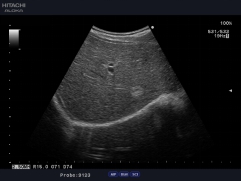

臨床圖例